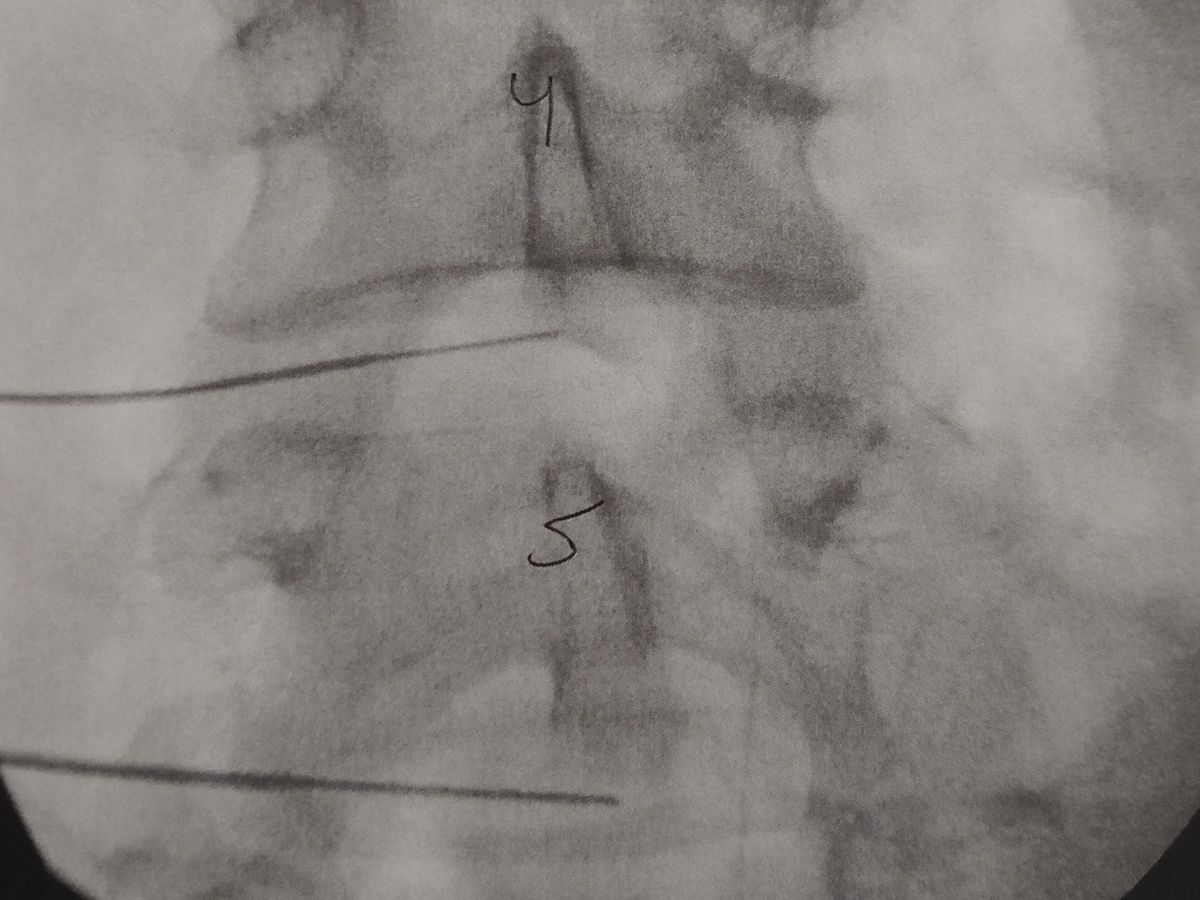

My wife has been battling chronic back pain for many years, she has been told by multiple surgeon's that she's "too young" for back pain, until finally she found a surgeon that looked at her like a patient, rather than her age. 5 of her discs have annular tears in them, at least 3 of them need it be replaced, insurance will cover 2, with a single level fusion later on, so that is what we are going with! Because she will be out of work is why we are starting this GoFundMe.

She will be out of work in February/March for at least a month possibly more, to have a double disc replacement. Her deductable and out of pocket are a minimum of $2500, that is not including the money she will be missing by being out of work. Any amount can help! I don't want her to stress about bills and student loans while she is trying to get her back fixed ❤️